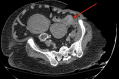

Necrotizing soft tissue infections are aggressive infections that cause necrosis of muscle, fascia, and tissue. They typically follow fascial planes that lack insufficient blood supply. Early drainage and debridement are essential for survival in these patients. This is a case of a patient who presented in diabetic ketoacidosis with a necrotizing soft tissue infection localized to the left flank and abdomen with underlying colon cancer pathology. The patient was a 54-year-old female who initially presented with acute dyspnea and left flank pain for two weeks. On admission, she was afebrile, tachycardic, tachypneic, and hypertensive. After being transferred to the ICU for diabetic ketoacidosis management, she began complaining of left abdominal pain and the CT showed concerns for a possible necrotizing soft tissue infection in the left flank region. She was taken to the operating room immediately for debridement and started on broad-spectrum antibiotics. The next day, an exploratory laparotomy was performed with a hemicolectomy and creation of an end colostomy due to concern for a perforated colonic malignancy. A final debridement was completed and a wound vacuum-assisted closure (VAC) was placed. Final pathology demonstrated well-differentiated colonic adenocarcinoma invading into the muscularis propria. Overall, necrotizing soft tissue infections can be related to a perforated viscus especially a colonic malignancy and this case demonstrates the importance of proper surgical management and high clinical suspicion for possible underlying pathology in a soft tissue infection.